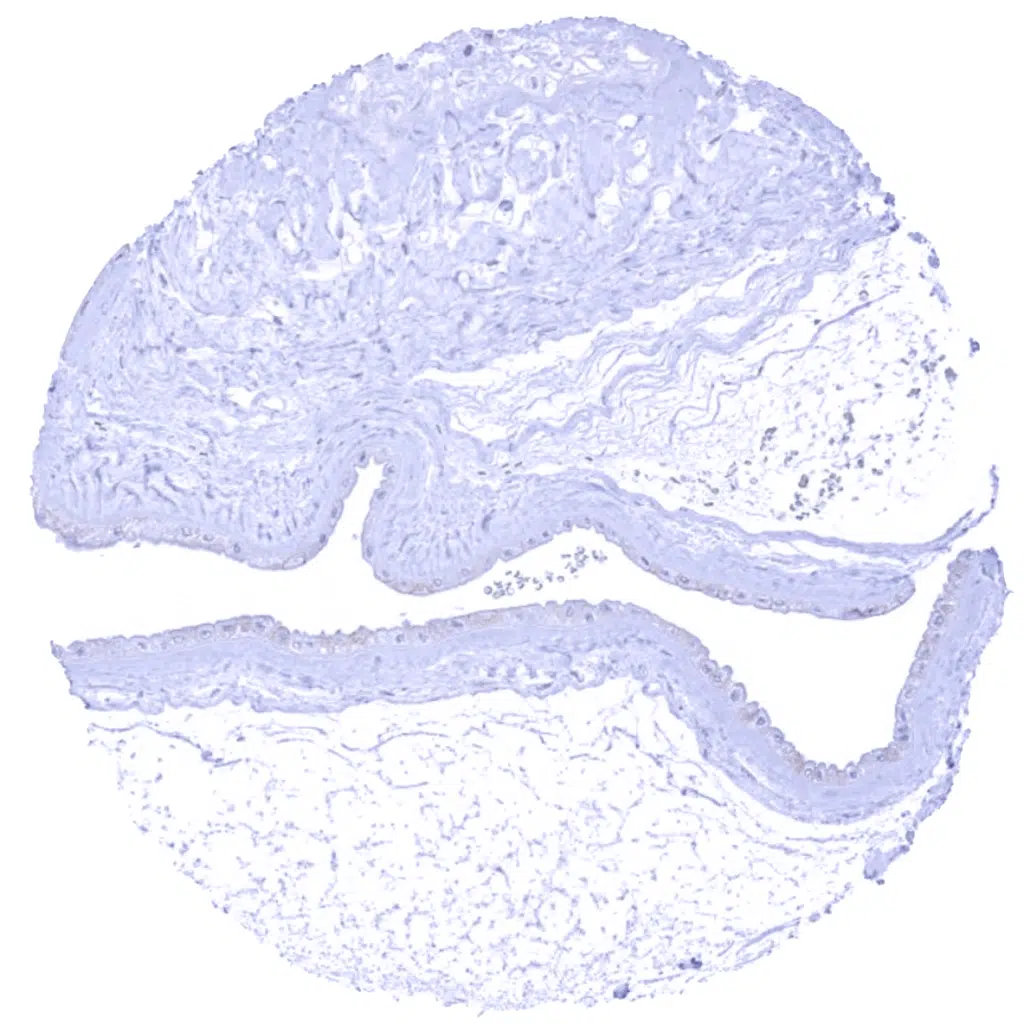

Uterus, ectocervix – Significant membranous Dsg3 immunostaining of all cell layers.

Uterus, endocervix